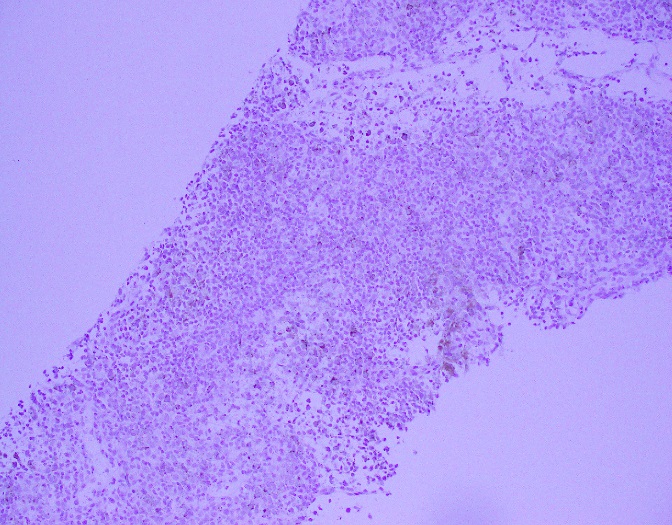

Histologically, the tumor consisted of spindle cells arranged in a fascicular pattern with intermittent whorled areas. The cells contained pleomorphic, hyperchromatic nuclei and intervening myxoid hypocellular areas. Mitotic figures were observed with sparse areas of necrosis and hemorrhage. S-100 was ordered on the prior biopsy of the mass, which was weakly positive. Based on these findings, the specimen was signed out as a malignant peripheral nerve sheath tumor.

Grossly, MPNST will present as a large, poorly defined, fleshy tumor that runs along a nerve and involves adjacent soft tissue. Often, these tumors will have areas of hemorrhage or necrosis and can track along the length of a nerve. Histologically, the tumors are composed of monomorphic spindle cells arranged in fascicles, palisades and whorls, with compact comma-shaped, wavy or buckled hyperchromatic nuclei with alternating hypocellular foci. (Image 3 and 4). Mitotic figures and necrosis are common, and although S-100 is considered the best marker for MPNST, there is a lack of specificity and sensitivity for immunohistochemical markers. Due to the lack of immunohistochemical markers and molecular findings, as well as the variability associated with the cells, it has traditionally been difficult to diagnose MPNST. The differential diagnosis includes fibrosarcoma, monophasic synovial sarcoma, desmoplastic melanoma, and pleomorphic liposarcoma. Goldblum et al put forth the idea that a diagnosis of MPNST can be made if the tumor falls into any one of the following three categories: